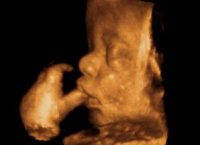

При необходимости вмешательств возможно использование новейших безболезненных методик с использованием лазера и криогенных технологий. Для ультразвуковых исследований применяют новейший ультразвуковой сканер с допплером и 3D | 4D визуализацией GE Healthcare пр-ва 2016 года (США) премиум-класса - это полностью цифровая универсальная цветная ультразвуковая система, построенная с использованием технологии TruScan - эксклюзивной технологии GE, обеспечивающей непревзойденное качество изображения, расширенные возможности обработки данных и высочайший уровень эргономики.

ComfortScan - новый подход к созданию УЗ систем с высочайшим уровнем эргономики для обеспечения максимального комфорта пациента и пользователя, имеет постоянно-волновой допплер, цветовое картирование и функции 3D и 4D визуализации, с возможностью автоматического трехмерного сканирования в режиме реального времени с использованием специализированных датчиков, а также дуплексные и триплексные исследования. Благодаря множеству инноваций и инженерных решений, применённых в данной системе появилась возможность высокоточных, безвредных ультразвуковых исследований Premium-класса как при уточнении диагноза, так и при скринингах беременных на любом сроке с возможностью оценки кровотока, допплерографии, цервикометрии, 3D и 4D визуализации с возможностью первой записи Вашего малыша на диск или другой носитель.